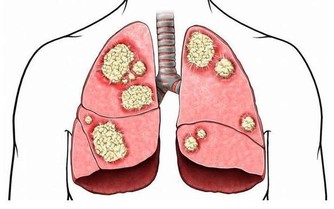

人體缺乏鈣質時,其實害怕的是血液含鈣量不足,以致於影響身體機能,醫學上稱為低血鈣症,它從神經的傳導訊息到內分泌,甚至是肌肉收縮都有關係。通常低血鈣症會影響三種肌肉:

骨骼肌:缺鈣會讓人肌肉緊繃,無法放鬆。

平滑肌:缺鈣時心臟會亂跳,反而會心律不整,有時可會導致猝死問題。

心肌:與腸胃道的蠕動跟吸收及血管有關,會影響血管收縮。